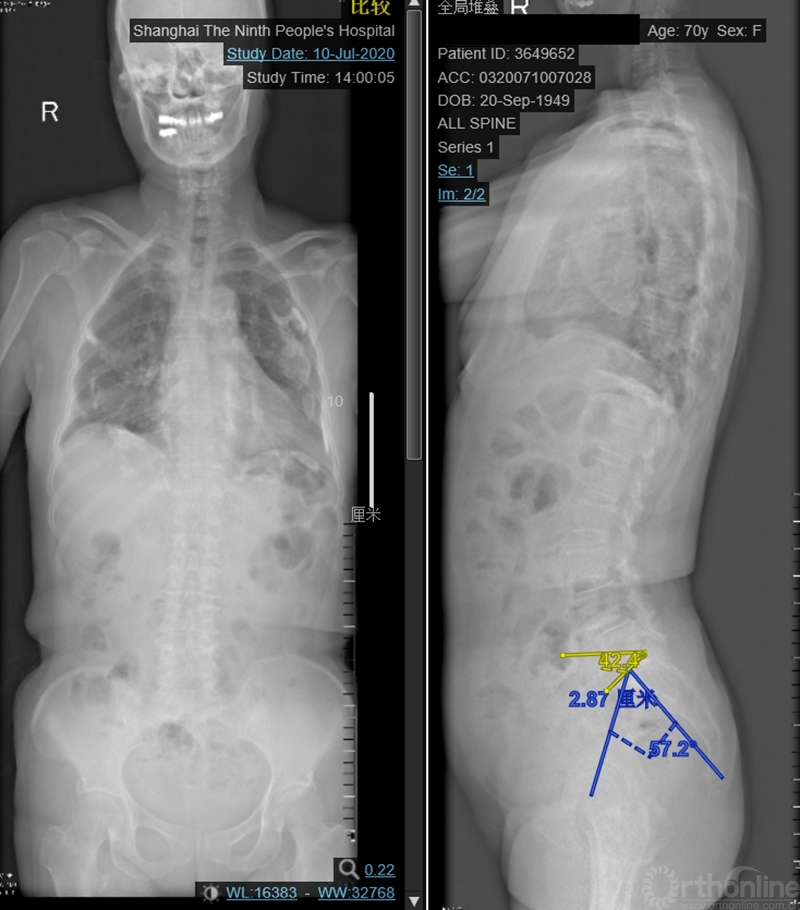

本文提供一例病例,高PI的腰椎显著前凸多节段的腰椎管狭窄症合并腰椎滑脱的患者(PI:57度,LL: 62度,图1、2、3),术前影像显示腰3-4、4-5椎管狭窄、椎体滑脱(图2、3),术前临床表现为右侧下肢麻木无力症状,术中接受了双节段MIS-TLIF手术。

图1:术前脊柱全长片:PI:57°、SS:42°

图2:术前腰椎正侧位:腰3-4、4-5滑脱。腰椎矢状面顶椎腰23椎间隙,LL:62°,L34椎间隙与水平成角度21°,L45椎间隙与水平成角26°,椎间隙方向为术中工作通道方向。